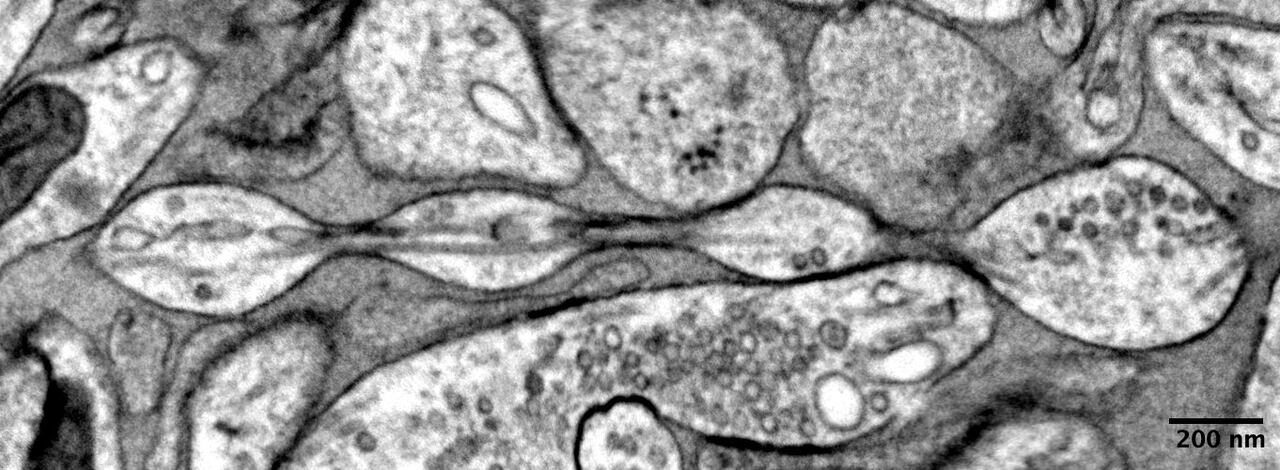

진주를 여러 개 엮은 듯한 축삭의 구조./네이처 신경과학

미국 존스홉킨스대 의대 연구진은 2일 포유류의 뇌세포 축삭의 구조가 진주를 엮은 목걸이 형태일 가능성을 제기했다. 연구 결과는 이날 국제 학술지 '네이처(Nature) 신경과학'에 게재됐다.

인간 머리카락 두께의 100분의 1 크기인 축삭은 100년 넘게 지름이 일정한 원통 형태로 묘사됐다. 간혹 신경 전달 물질을 보관하는 거품 모양의 돌기가 관찰되긴 했으나, 일반적이지 않다고 여겨졌다.

연구진은 실험실에서 배양한 쥐 신경세포, 쥐의 성체에서 채취한 신경세포, 쥐 배아에서 얻은 신경세포의 축삭을 각각 관찰했다. 다양한 유형의 신경 세포에서 축삭이 원통형 구조가 아닌 진주가 엮인 모양과 비슷한 것을 발견했다.